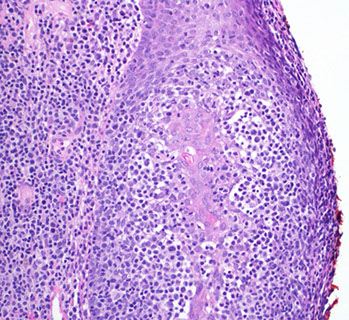

Lymphoblastic lymphoma, the cytology not predictive of phenoty[e (left is B-cell, right is T-cell, or maybe vice versa? you would never know)

TdT is important in the diagnosis of lymphoblastic lymphomas, positive here in lymphoblasts around a germinal center (left) can also be used in cytology (right)